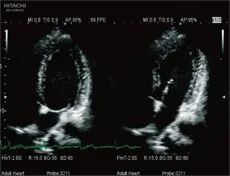

(Dynamic Slow-motion Display)

通过对实时画面的逐帧对比,极速捕捉异常信息并慢放成像,用于快速运动脏器特别是对心脏的观察,把握瞬息变化,减少漏诊和误诊。

模式匹配技术准确识别并跟踪感兴趣的点,智能化分析心肌节段运动,准确评估心肌局部运动功能及各节段运动的协调性,构建左室“牛眼图”,更加直观显示心室整体功能状态。